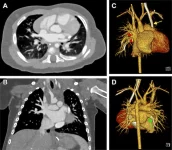

Может ли КТ с подсчетом фотонов повлиять на диагностику врожденных пороков сердца у детей раннего возраста?

Компьютерная томография со счетом фотонов (ПККТ) значительно увеличила отношение сигнал-шум (SNR) и контраст-шум (CNR) по сравнению с КТ с двумя […]… далее